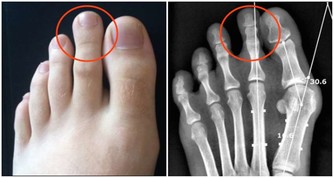

1、去醫院拍片確定關節損傷情況。

4、若因骨刺引起關節疼痛,可以用手術方法切除骨刺,也可採用微創療法。